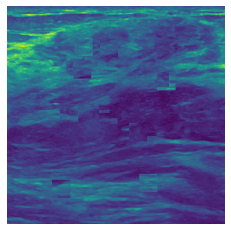

In figure 3, we present qualitative examples of different masking strategies. It is observed that, unlike context prediction and restoration, our method tends to propose targeted masks like the tumor regions or regions with abnormalities and avoids masking less helpful regions. However, it should be noted that Intelligent-Masking does not necessarily mask the tumor regions but considers all areas of interest that results in better feature learning. Examples of other masking samples are provided in supplementary materials. Furthermore, in medical images, unlike natural scenes, the structures are very local with imbalanced information throughout an image. Therefore, random masking strategies as shown in Fig 3 operate ineffectively by masking non-informative regions.

Refer to caption

(a) Original

(b) Intelligent-Masking

(c) Context Prediction

(d) Context Restoration

Figure 2: Qualitative examples of compared method’s strategies for masking